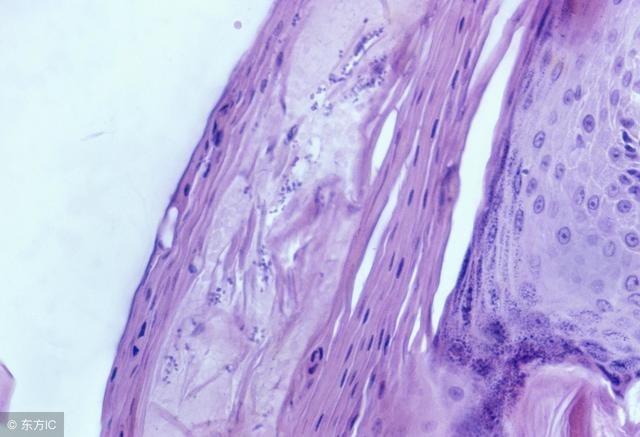

毛囊炎在初期的时候皮肤会出现与毛囊口一致的红色充实性丘疹或者毛囊性脓疱疮,如果不及时进行治疗,慢慢的就会发展演变成丘疹性脓包,如果经常用手抓挠,会加速形成小脓包,脓包中间会贯穿毛发,四周红晕而且有炎症,接着脓包会干燥结痂,大概一周左右的时间结痂会脱掉伤口会恢复。情况严重的容易引起感染,这中情况需要多加注意,如果引起感染要及时进行治疗。毛囊炎对于成人来说常常发生于毛发多的部位,对于小孩子来说常常发生于头部,皮疹有时候可能会互相融合,恢复之后呈现小片状秃发斑。

粉刺又称“痤疮”、“酒刺”、“暗疮”等,是发生在毛囊皮脂腺的慢性皮肤病,多因毛孔堵塞所致,若形成顶为白色的丘疹,就称为白头粉刺。白头粉刺也称为白头,是毛囊漏斗部被角质层细胞堆积、堵塞,角质物和皮脂充塞其中

形成白色角质物丘疹,表面有表皮覆盖,与外界不相通,成为封闭式粉刺。好发于面部或颈部,一般为对称性分布,两侧多寡不定,无自觉症状。白头粉刺与粟丘疹不同。粟丘疹为表皮附属器的潴留性囊肿。本病在治疗上可用粉刺压出器将其挤出。